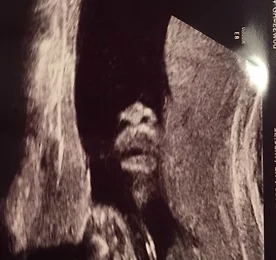

(1/6) 22주차, 잘크고 있는 금동이. 22주차에 들어서 오랜만의 정밀 초음파를 진행했다. 그간 태동도 신나게 해왔고, 태동놀이라면 놀이라고 할만한 정도의 - 서로간의 리액션도 나름 주고 받았지만 아직도 정감있는 대화나 표현이 서툰 예비 엄마인 나로서는..이 녀석은 괜찮게 자라고 있을까, 늘 확신은 없어 불안하기만 했었던 게 사실이다.그런데 그간 알게 모르게 걱정했던 것들이 무색하게도, 금동이는 또 이렇게 금방 커서 모든 장기도 다 잘 형성되고 주수에 맞는 사이즈로 건강히 잘 크고 있다고 한다.잘 챙겨주지 못한 것 같은데도 쑥쑥 커가고 있는 걸 보니 그저 신기할 뿐... 여기저기 검사하고 코와 입술 부분을 스윽 찍는데, 코가 완전 오빠랑 판박이다.ㅎㅎ 부정할 수 없는 유전자의 힘일까요...ㅎㅎ이제 40주의 반 지났는데 아직도 갈길이 먼 듯 하.. 더보기